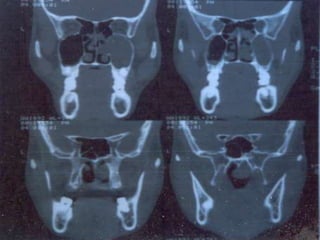

• X-ray PNS

• CT Scan PNS (Coronal and Axial views)

• Haematological TC, DC,Hb%, ESR Absolute eosinophil count • X-ray PNS • CT Scan PNS (Coronal and Axial views) DNE INVESTIGATIONS